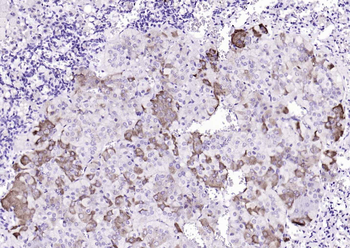

RARB Rabbit Polyclonal Antibody [orb11327]

FC, ICC, IF, IHC-Fr, IHC-P, WB

Bovine, Canine, Gallus, Porcine, Rat

Human, Mouse

Rabbit

Polyclonal

Unconjugated

50 μl, 100 μl, 200 μlTIG2 Rabbit Polyclonal Antibody [orb11481]